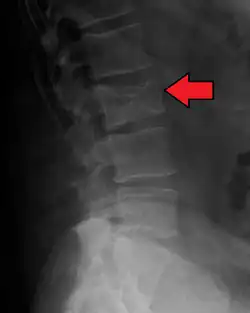

Pathological fracture of the lumbar spine due to multiple myeloma -

Bone pain affects almost 70% of people with multiple myeloma and is one of the most common symptoms.[2]: 653 [23] Myeloma bone pain usually involves the spine and ribs and worsens with activity. Persistent, localized pain may indicate a pathological bone fracture. Involvement of the vertebrae may lead to spinal cord compression or kyphosis. Myeloma bone disease is due to the overexpression of receptor activator for nuclear factor κ B ligand (RANKL) by bone marrow stroma. RANKL activates osteoclasts, which resorb bone. The resultant bone lesions are lytic (cause breakdown) in nature. They are best seen in plain radiographs, which may show "punched-out" resorptive lesions (including the "raindrop" appearance of the skull on radiography). The breakdown of bone also leads to the release of calcium ions into the blood, leading to hypercalcemia and its associated symptoms.[24]

The diagnostic examination of a person with suspected multiple myeloma typically includes a skeletal survey. This is a series of X-rays of the skull, axial skeleton, and proximal long bones. Myeloma activity sometimes appears as "lytic lesions" (with local disappearance of normal bone due to resorption) or as "punched-out lesions" on the skull X-ray ("raindrop skull"). Lesions may also be sclerotic, which is seen as radiodense.[76] Overall, the radiodensity of myeloma is between −30 and 120 Hounsfield units (HU).[77] Magnetic resonance imaging is more sensitive than simple X-rays in the detection of lytic lesions. An MRI may supersede a skeletal survey, especially when vertebral disease is suspected. Occasionally, a CT scan is performed to measure the size of soft-tissue plasmacytomas. Nuclear Medicine Bone scans are typically not of any additional value in the workup of people with myeloma (no new bone formation; lytic lesions not well visualized on nuclear bone scan).